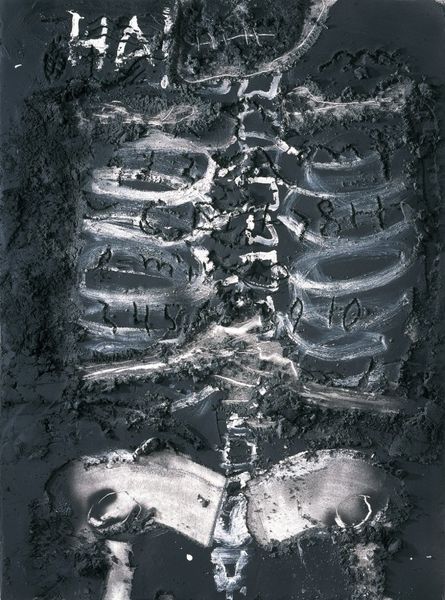

Swallowed Coin, Military Hospital by Anonymous

Swallowed Coin, Military Hospital 1918

photography, rayograph

Dimensions: image: 24.1 × 17.8 cm (9 1/2 × 7 in.) sheet: 23.6 × 17.9 cm (9 5/16 × 7 1/16 in.)

This peculiar image, "Swallowed Coin, Military Hospital," presents us with a striking interplay of form and function. Produced as a diagnostic tool, its aesthetic impact is undeniable. The composition is dominated by the stark contrast between the skeletal structure and the opaque disc lodged in the throat. Lines of the rib cage create a cage-like form, disrupted by the foreign object, which takes center stage. The materiality of the X-ray reveals layers of density. Light penetrates soft tissue, while bone and metal absorb it, creating a ghostly effect. There's a tension between the scientific purpose and the visual experience. The coin’s intrusion speaks to broader themes of disruption and the body. This radiographic image challenges our notions of inside and outside, public and private, and ultimately, the relationship between representation and reality.